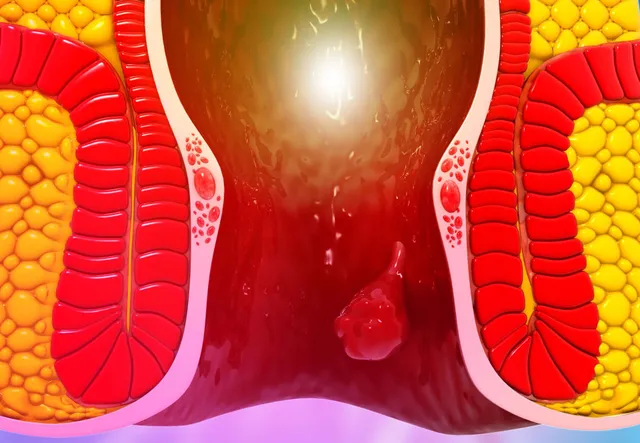

An anorectal abscess is a painful collection of pus near ...

Seeing blood during passing stool can be frightening ...

If you experience recurring pus discharge or pain around the anal ...

If you have been dealing with pain, swelling, or pus near the anus that keeps coming back ...